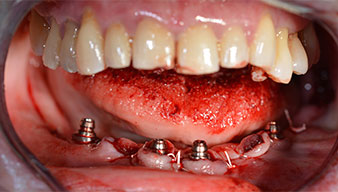

Angled abutments (35°) were screwed in to compensate for the divergence of the distal implants, with the result that the emergence profile of all implants was as perpendicular as possible to the bite plane. This is a prerequisite for occlusal placement of the provisional and subsequently the permanent denture (Fig. 15 and 16).

Implants

Fig. 15

Fig. 16

The impression and bite registration were then performed so that the dental technician could begin producing the provisional restoration immediately. This was then screwed in on the same day (Fig. 17 and 18).

Fig. 17